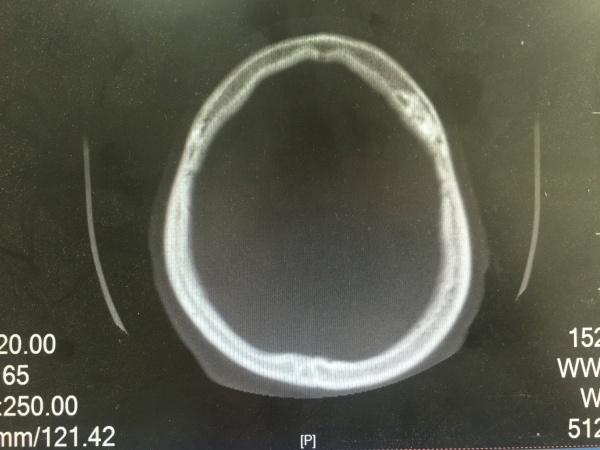

昨夜一位醉酒后外伤的病人,予以头颅CT检查发现的颅骨骨瘤,看着像在板障内,因患者醒酒后家属已送其回家,询问平素无明显不适,故无法跟踪及进一步明确。

请爱友们发言,考虑何种性质?